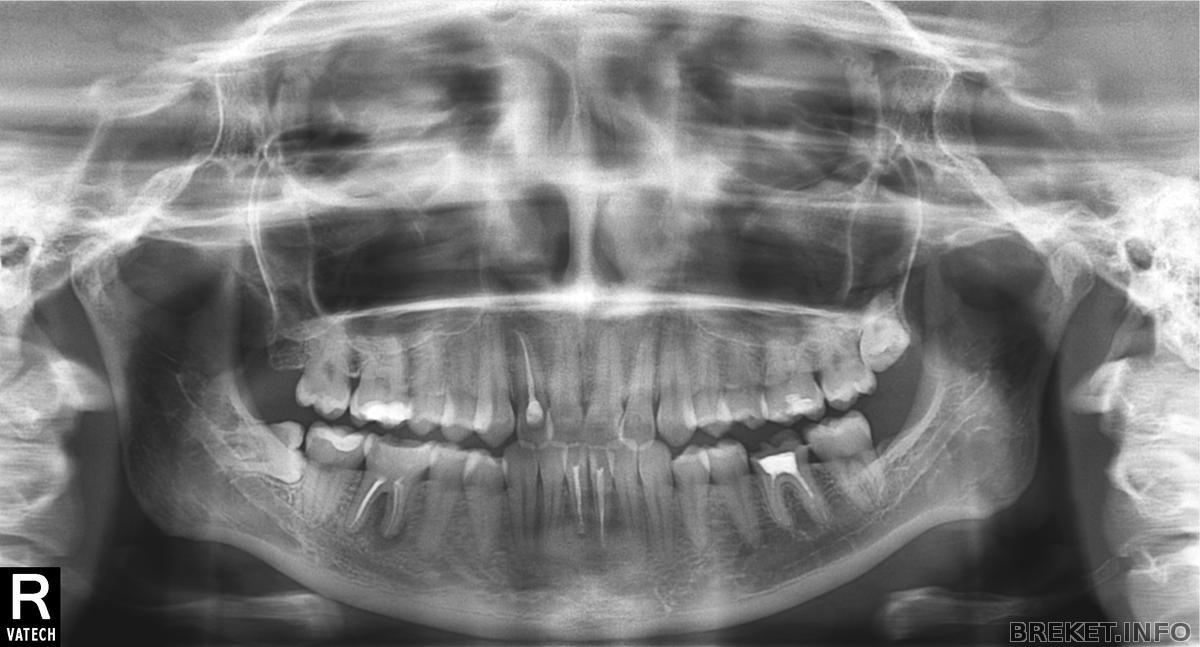

Reflections А можно кстати твою Оптг посмотреть?